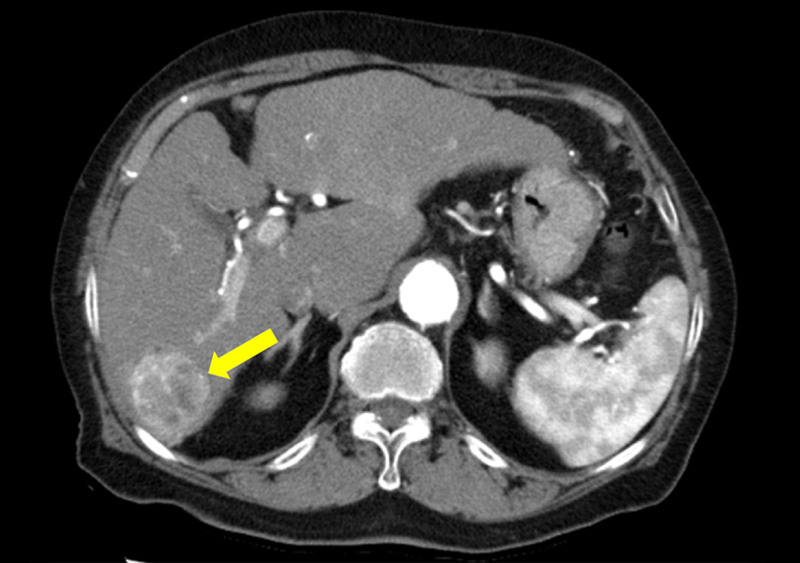

肝細胞癌の症例

造影CTで、肝臓に造影増強する肝細胞癌が描出されている(左図)。肝臓の血管を抽出した3D像では、肝細胞癌を形作る血管が描出されている(右図)。